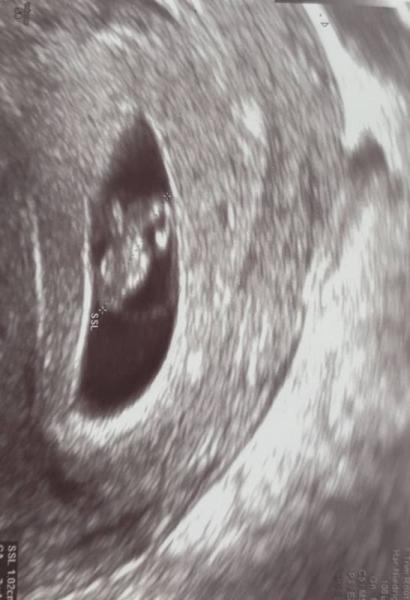

Hallo ihr Lieben, Hatte heute meinen 2ten FA Termin. Bin bei 7+1 Das Herzchen war deutlich zu sehen. Habe auch mein Mutterpass bekommen :) Der Zwerg ist ca 1 cm ET 22.01.2020 Morgen fliege ich in Urlaub, aber ich bin zuversichtlich das alles glatt läuft auch wenn meine FÄ heute nochmal gesagt hat das sie generell im 1 Trimester von Fliegen abraten .... Habe bislang aber immer noch keine großartigen Anzeichen. Außer der tägliche Schwindel... sollte wohl froh drüber sein. Aber ich fühle mich dadurch einfach noch so unschwanger... Wie sieht es bei euch aus? Und wann erzählt ihr es euren Freunden/ Familien? Bin am überlegen es schon dieses Wochenende zu erzählen. Wünsche jedem einzelnen alles Gute und eine hoffentlich angenehme/erträgliche Kugelzeit.

Bild zu 2 FA Termin - Forum für Januar - Mamis